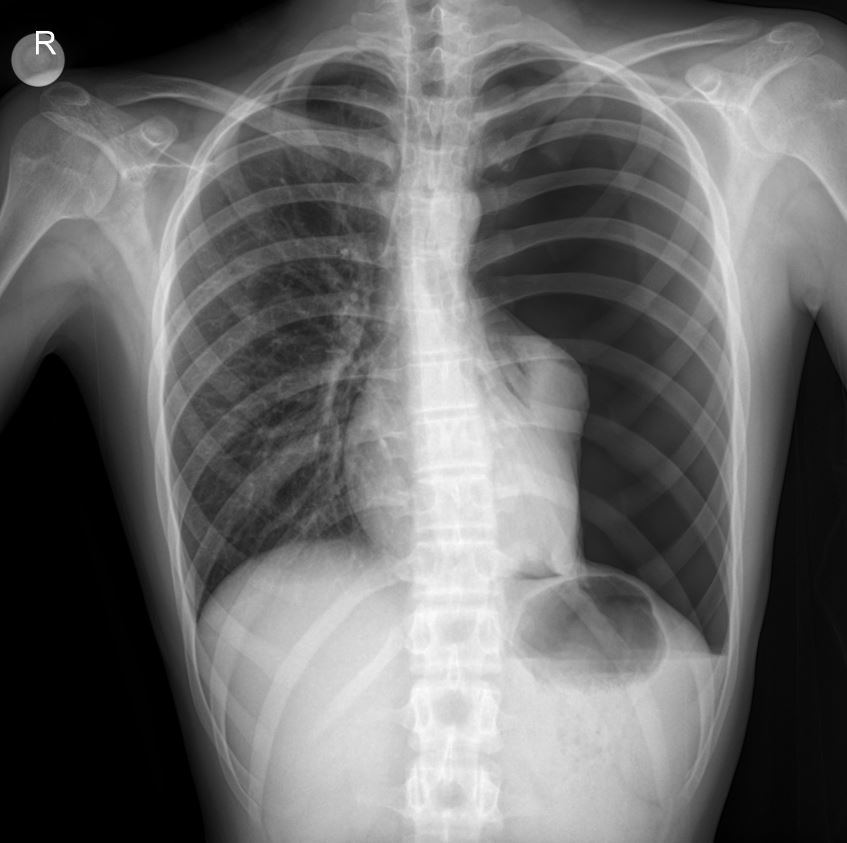

The provided chest X-ray image is highly demonstrative of a left total pneumothorax.

- Absence of Lung Markings: Crucially, there is a complete absence of vascular markings in the left hemithorax, indicating that the lung has fully collapsed.

- Visceral Pleural Line: A distinct, thin white line (indicated by the white line in the image) can be seen outlining the collapsed left lung, which is retracted towards the hilum. This line represents the visceral pleura.

- Hyperlucent Left Hemithorax: The left chest cavity appears hyperlucent (darker) compared to the right, due to the presence of air in the pleural space.

- Mediastinal Shift: While subtle, there may be a slight shift of the mediastinum (heart and trachea) towards the right, although this is less pronounced in a simple pneumothorax compared to a tension pneumothorax.

- Diaphragmatic Depression: The left hemidiaphragm may appear slightly depressed.

These radiological findings are pathognomonic for a total pneumothorax and correlate perfectly with the clinical finding of absent breath sounds on the left side.